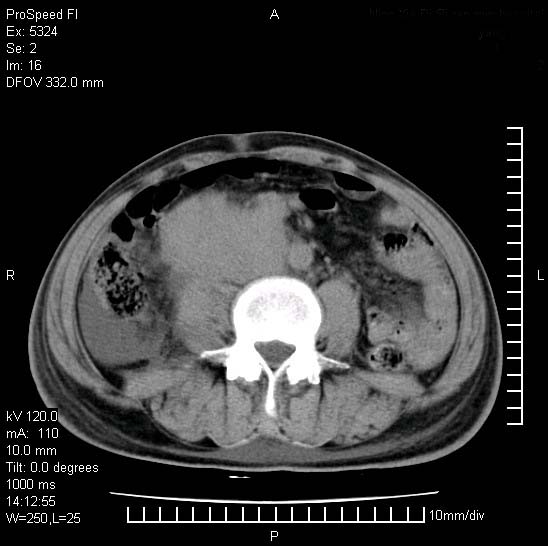

患者阴囊肿大14月,腰痛2个月,咳嗽,咳痰1周,患者现在肾功异常,做增强有些担心,我们用的是欧乃派克.

双肾均有软组织密度舯物,腹膜后淋巴结肿大包饶腔静脉------考虑为恶性占位病变,转移瘤可能。

支持:双肾均见软组织密度肿块影,腹膜后淋巴结肿大包绕腔静脉------考虑为恶性占位病变,转移瘤可能。

腹腔积液,双肾均有稍高密度肿块,主动脉旁广泛淋巴结肿大,融合,无显著肿块坏死征像,多考虑淋巴瘤累及双肾,不排除肾癌伴转移(肾癌这么大应该较多坏死了),另阴囊肿大,不知是实质肿大还是阴囊积液,如是是积液,多为腹腔肿块压近睾丸静脉所致,如是是实性的,多为淋巴瘤

阴囊肿大是实质性的么,为什么不扫阴囊,此扫描做的是什么部位,肾脏没包括全,也可以考虑生殖系统肿瘤转移

双肾增大,腹膜后多发肿大淋巴结影.首先考虑淋巴瘤.

双肾增大,结合腹膜后淋巴结肿大,考虑双肾恶性肿瘤并转移可能。